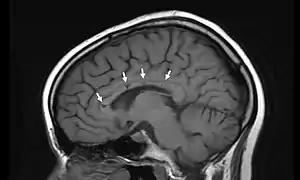

Sagittal T1 image in a 19-year-old woman with Susac's syndrome showing the pathognomonic central callosal "holes" (microinfarcts) of SS. These residual "holes" (and sometimes, "spokes") develop as the acute callosal changes resolve.